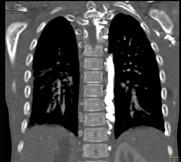

问题 下面一组图像显示的是 ( )

选项 A、奇静脉增粗可见于各种病因引起的上腔静脉梗阻 B、奇静脉增粗可见于各种病因引起的下腔静脉梗阻 C、正常的奇静脉干直径小于1.0cm D、奇静脉弓层面其直径小于1.2cm E、奇静脉扩张

答案 ACDE